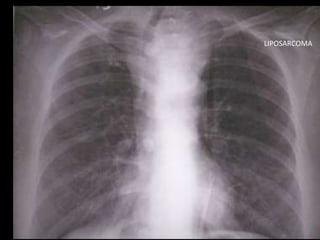

LIPOSARCOMA

• Mesenquimáticos: lipomas, liposarcomas, lipomatosis,

fibromas, hemangiomas, linfangiomas